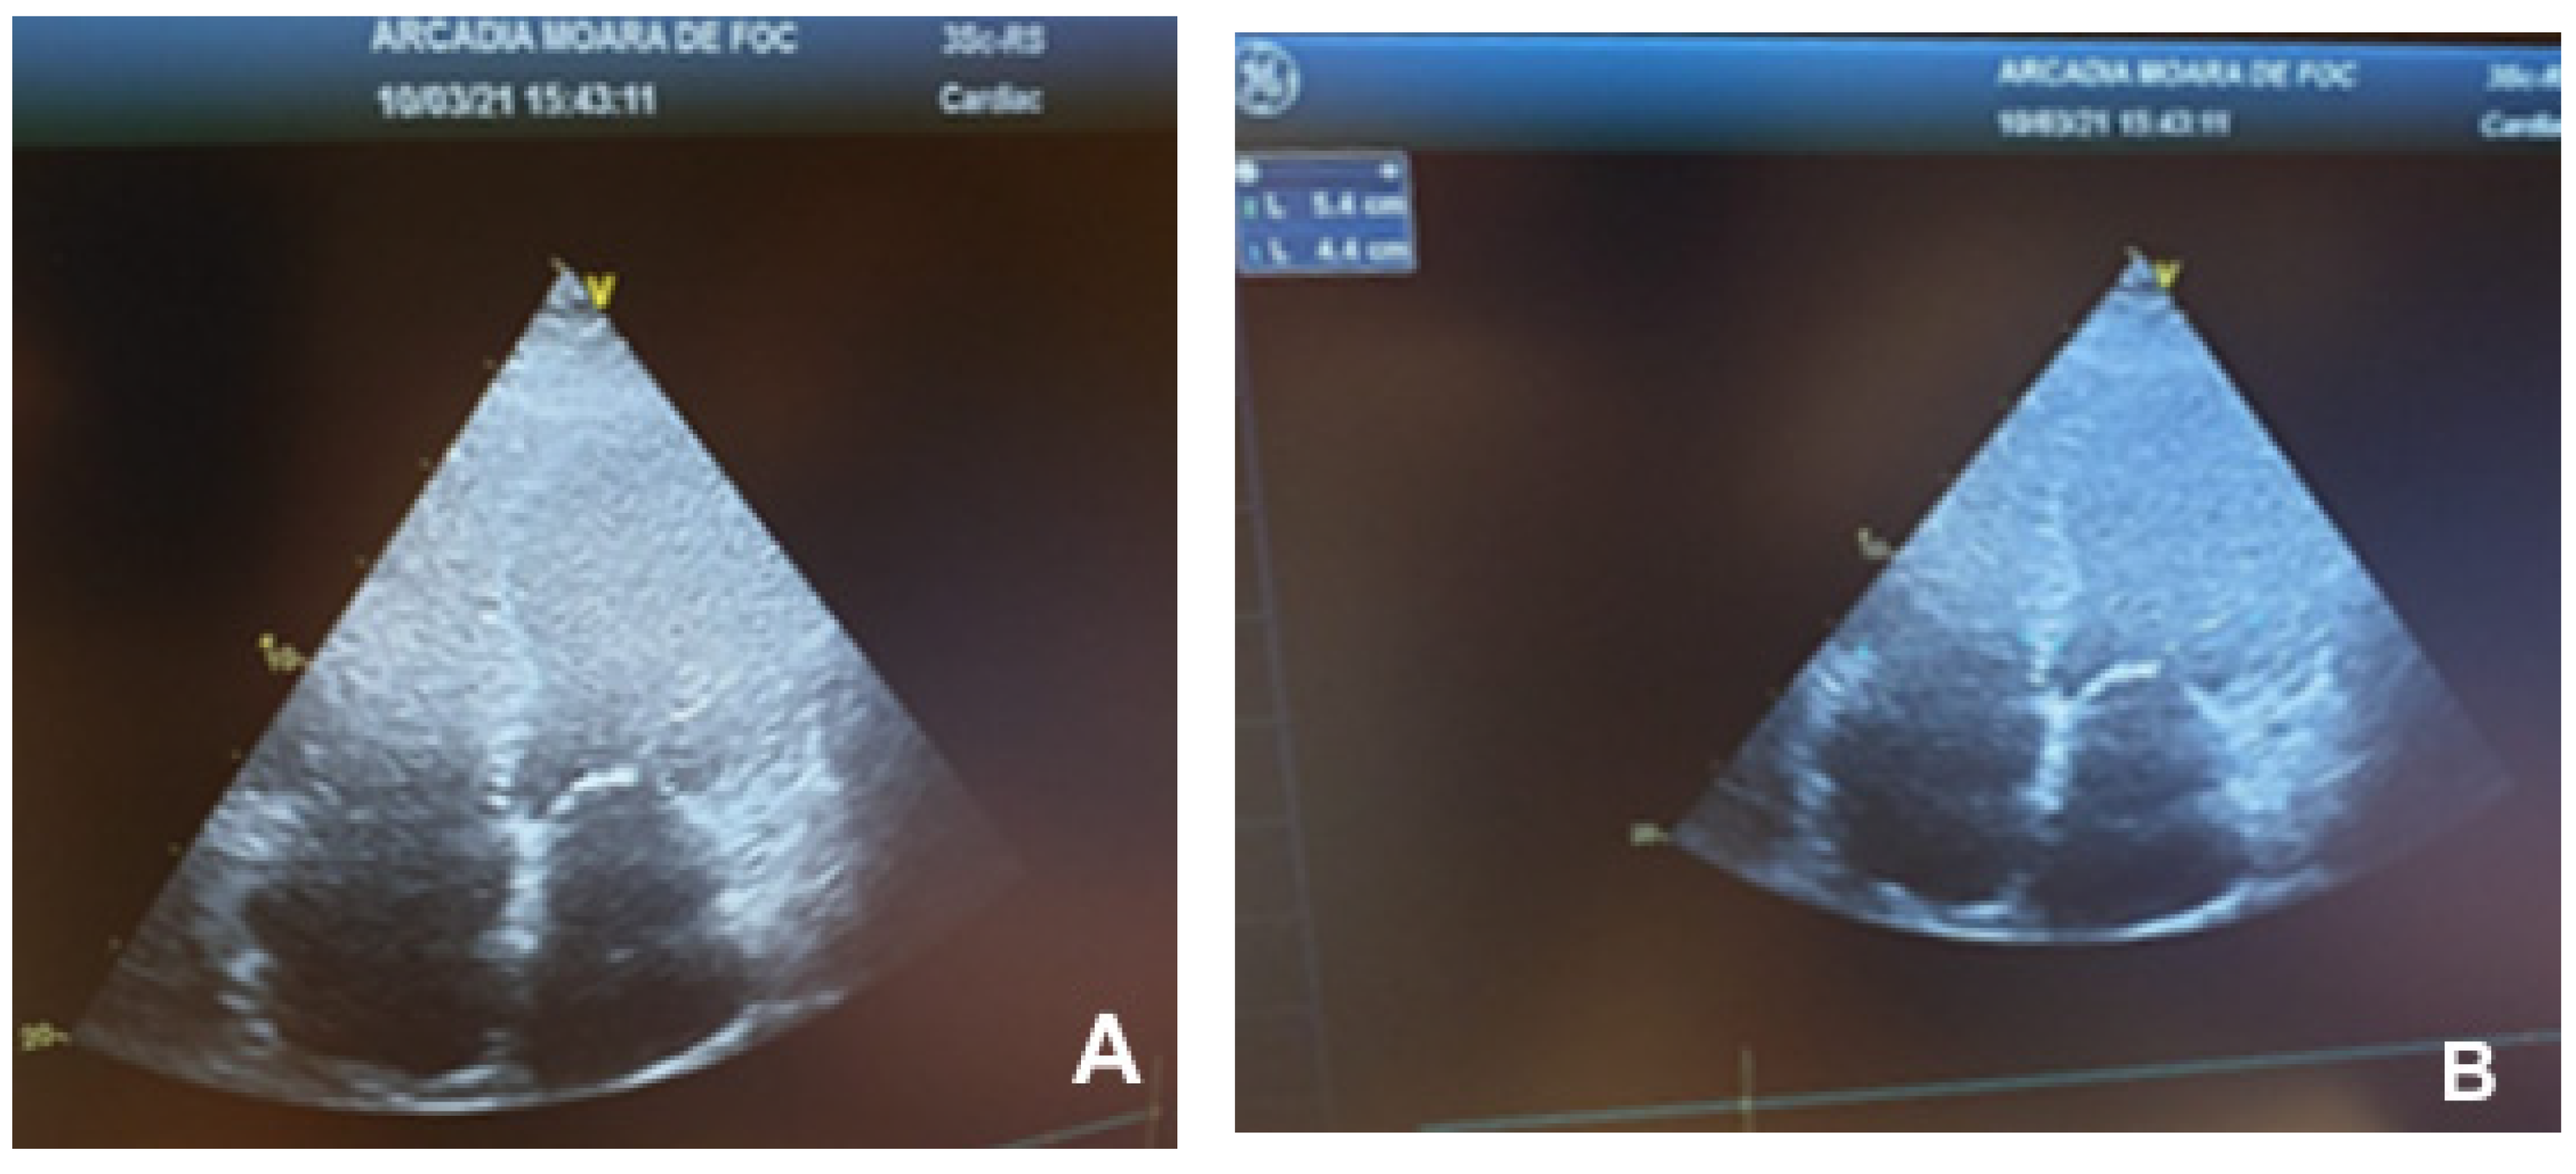

5.5. Echocardiography